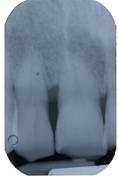

Pre-operative periapical radiography with a Rinn Centering was performed [fig. 1].

Fig 1

Pre-operative periapical radiography

The examination technique was standardized to obtain radiographs as similar as possible. Impressions were made at the first examination and saved for follow-up control examinations. Radiographs were performed immediately before treatment and at 10 days, and 6, 9, and 24 months after treatment.